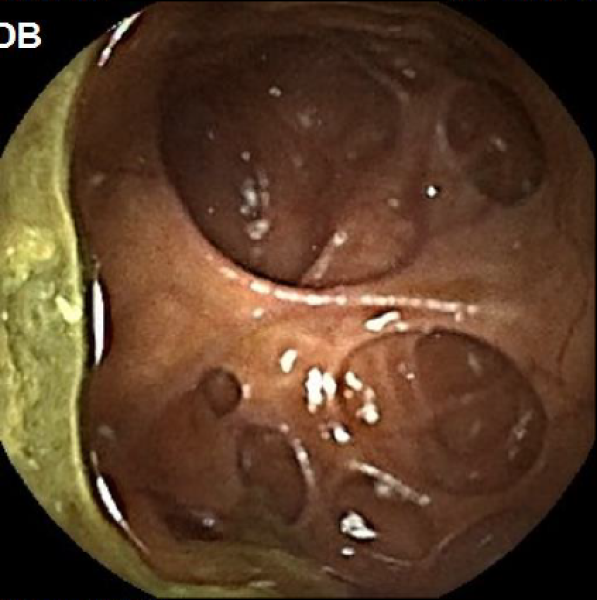

[1º CLASSIFICADO] From the ileum to the stoma - Silent multiple lymphomatous polyposis in mantle cell lymphoma

Fotografia